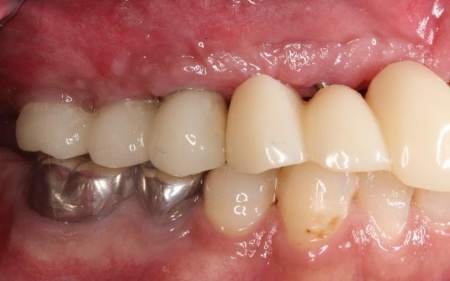

また、インプラント治療と並行して、合わなくなっていた被せ物・詰め物・既存のインプラントを作り替えます。

左上奥歯は、装着されていた金属の古い詰め物を外し、白い樹脂を直接詰める「ダイレクトボンディング」で修復しました。

他院で治療を行った左下奥歯3本のインプラントは、土台をそのまま活かして人工歯だけ作り直し、噛み合わせを調整します。

左下奥歯1本、右下奥歯2本に装着されていた古い被せ物はすべて外し、ジルコニアクラウンと交換しました。

最後に、見た目や噛み合わせに問題がないかを確認し、治療を終了しています。